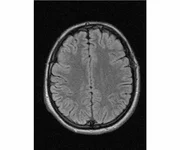

делал в обласной на siemense.В заключении выданом мне через 15мин.после мрт (легкая дегидрация)

Меня смутил факт выдачи заключения через 10мин(наверно они у них зарание напечатаные)я не медик.достаточно мимолётного взгляда на снимки?А вы видете на них гидроцефалию? Я лиш спросил куда идти с результатами томографии?и не хотел никого роздражать.

Я попросил взглянуть на снимки и сказать видна.ли на них гидроцефалия?или куда обратится за консультацией по этому вопросу?В мрт снимках наверно розбирается любой нервопатолог(я так предположил)

Я уже говорил, что независимо от того, есть на МРТ гидроцефалия или нет, лечиться тебе нужно только в том случае, если есть какие-либо проявления болезни, иначе на все эти анализы можешь забить... Но давай все-таки разберемся с томограммой.

Итак, с самого начала томограмма обозначала срез какого-либо органа на определенной глубине, позволяла заглянуть вовнутрь. При компьютерной томографии аппарат делает десятки срезов головного мозга в разных направлениях и из этого множества срезов он моделирует полноценное объемное изображение мозга в натуральную величину. Обрати внимание, компьютер работает не с этими миниатюрными изображениями, а с трехмерной моделью в масштабе 1:1. Эту модель вдоль и поперек анализирует суперсовременный компьютер, выполняющий миллионы операций в секунду. Только ***** может пытаться перепроверить компьютер, ведь человеку не хватит всей жизни чтобы проанализировать то, что компьютер с тобой сделал за 10 минут. Я хочу, чтобы ты это понял!

Ты разместл здесь несколько миниатюр и хочешь, чтобы врач по ним создал полноценное объемное изображение в натуральную величину, а потом осмотрел его со всех сторон и дал заключение? Но ведь это невозможно. Это просто насмешка над врачом, это издевательство над здравым смыслом. Принеси Букеру уменьшенный в 50 раз снимок зуба и спроси у него, в каком состоянии там корневые каналы. Или давай я дам тебе скрин со спутниковой карты города и попрошу тебя описать, какого цвета и какой модели запечатленная со спутника машина, какой у нее гос.номер, сколько в ней пассажиров, сколько из них мужчин и сколько женщин...

Надеюсь, ты понимаешь, что это невозможно. И воссоздать по приведенным тобой аватарам полную картину мозга тоже невозможно. Пойми, если уж называть вещи своими именами, то ты запостил полнейшую ***ню! Ты не хотел никого обидеть, ты ведь сам не ведал, что творил. Ты продемонстрировал полнейшую медицинскую безграмотность и полное невежество, но претензий к тебе нет. Ты ведь не один такой. Ты пожелал того, что сделать невозможно, и тут же у тебя нашлась сочувствующая, некая П., которую, по большому счету, надо бы послать в П., коль уж она считает, что врач должен тут сделать немедленно и бесплатно то, что делает немецкий компьютерный томограф ценой в миллионы долларов.